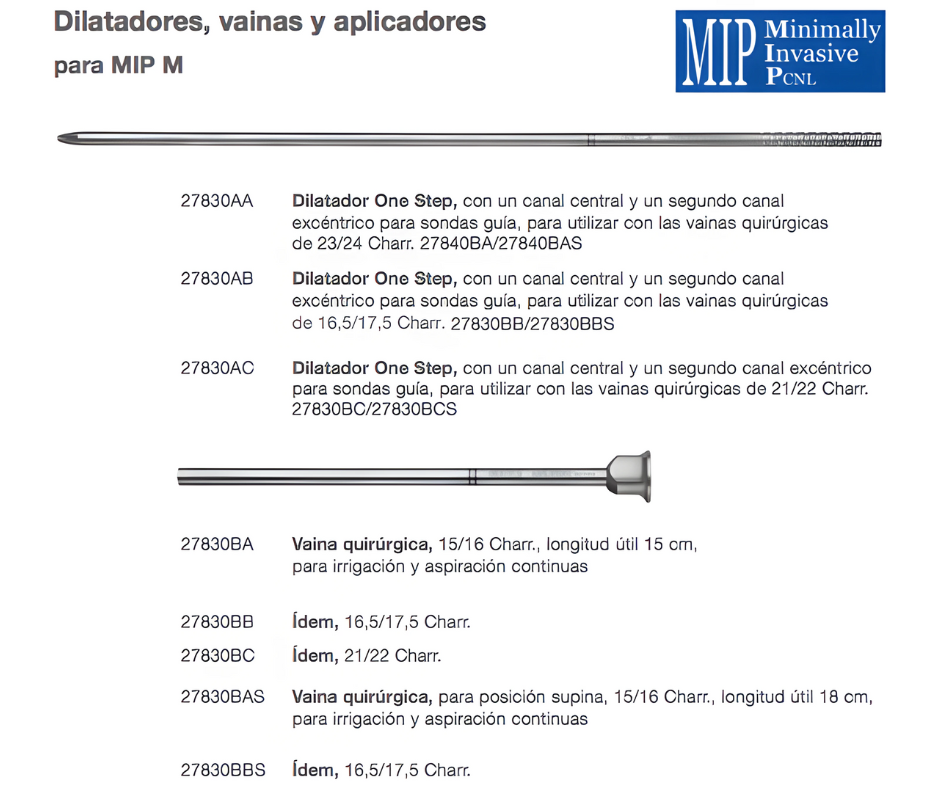

Tras la incisión cutánea, se ensancha el acceso con un solo dilatador hasta el punto de que la vaina se pueda deslizar hasta el riñón, ya no es necesario recurrir a los dilatadores telescópicos o los dilatadores de varios tamaños.